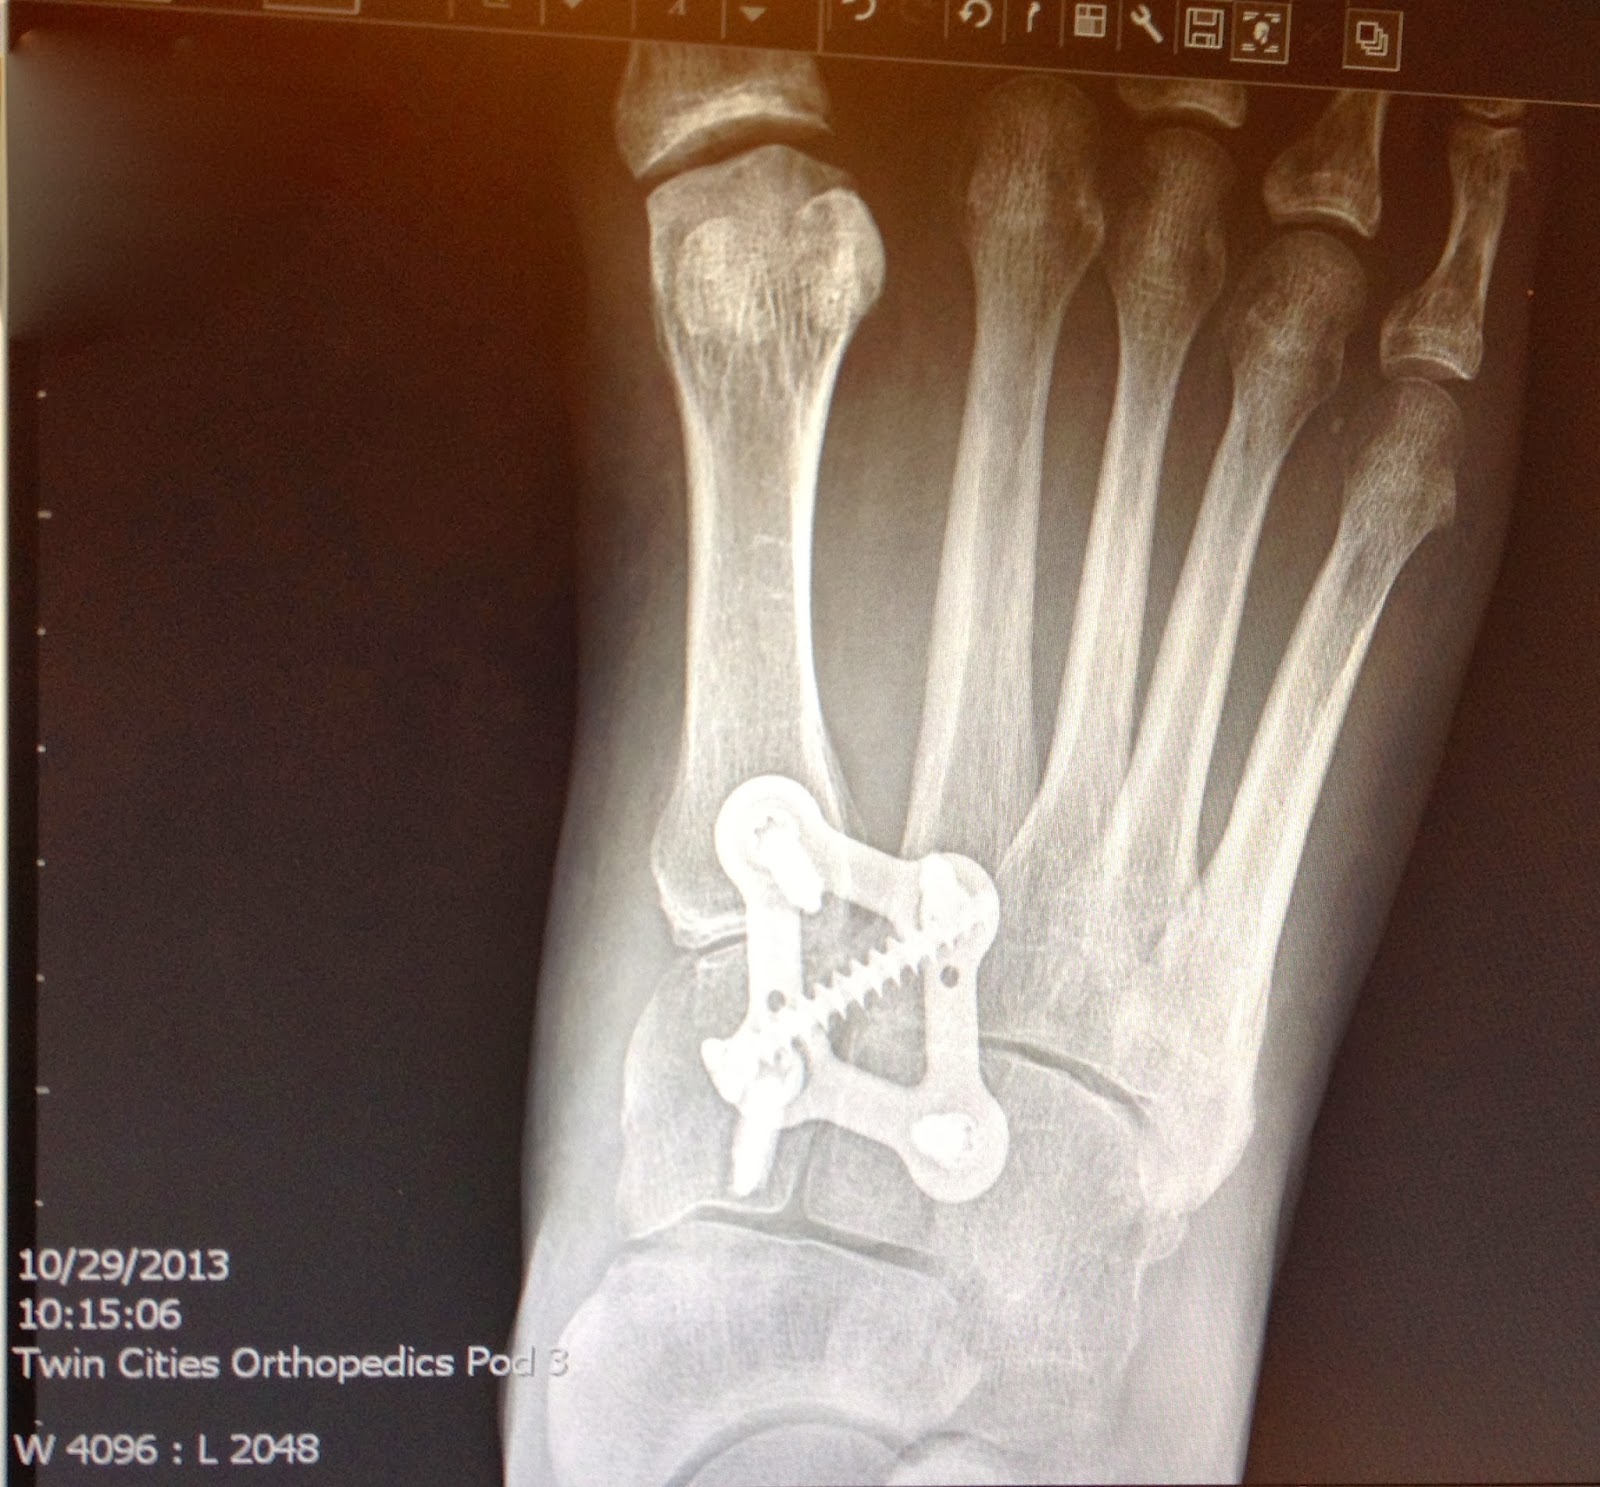

After LisFranc Surgery 23 weeks post lisfranc surgery Recovery After Lisfranc Surgery Web recovery after surgery after reduction of the fracture, your foot will need to be immobilized to allow for the broken. You should elevate the foot as. This protects the bones and incisions. Lisfranc injury can be quite serious and require months to heal. Web what happens after surgery on the lisfranc joint? Web recovering from a lisfranc fracture and. Recovery After Lisfranc Surgery.

After LisFranc Surgery 15 weeks post lisfranc surgery Recovery After Lisfranc Surgery Here's how i coped during the first six weeks, a period of limited. Lisfranc injury can be quite serious and require months to heal. You should elevate the foot as. This protects the bones and incisions. Web what happens after surgery on the lisfranc joint? The foot will be in a cast or a boot, and patients can use a. Recovery After Lisfranc Surgery.

After LisFranc Surgery 10 weeks post lisfranc surgery Recovery After Lisfranc Surgery Web what happens after surgery on the lisfranc joint? For those experiencing strains or sprains, recovery could take six to eight weeks. Here's how i coped during the first six weeks, a period of limited. Web recovering from a lisfranc fracture and surgery takes months, or even years. For those needing surgery, recovery will likely take three to five months.. Recovery After Lisfranc Surgery.

After LisFranc Surgery 25 weeks post lisfranc surgery Recovery After Lisfranc Surgery Web recovery after surgery after reduction of the fracture, your foot will need to be immobilized to allow for the broken. Web overcoming lisfranc injury and reconstructive surgery is one of the biggest challenges some people will ever face. For those needing surgery, recovery will likely take three to five months. Web what happens after surgery on the lisfranc joint?. Recovery After Lisfranc Surgery.

After LisFranc Surgery 22 weeks post lisfranc surgery Recovery After Lisfranc Surgery The foot will be in a cast or a boot, and patients can use a scooter or crutches to keep weight off it. This protects the bones and incisions. You should elevate the foot as. For those needing surgery, recovery will likely take three to five months. Web how long does it take to recover from lisfranc injury? Web recovering. Recovery After Lisfranc Surgery.

After LisFranc Surgery 2013 Recovery After Lisfranc Surgery For those needing surgery, recovery will likely take three to five months. Web overcoming lisfranc injury and reconstructive surgery is one of the biggest challenges some people will ever face. Lisfranc injury can be quite serious and require months to heal. This protects the bones and incisions. Web how long does it take to recover from lisfranc injury? Web recovery. Recovery After Lisfranc Surgery.

After LisFranc Surgery 11 weeks post lisfranc surgery Recovery After Lisfranc Surgery The foot will be in a cast or a boot, and patients can use a scooter or crutches to keep weight off it. For those experiencing strains or sprains, recovery could take six to eight weeks. Web what happens after surgery on the lisfranc joint? Lisfranc injury can be quite serious and require months to heal. Web recovery after surgery. Recovery After Lisfranc Surgery.